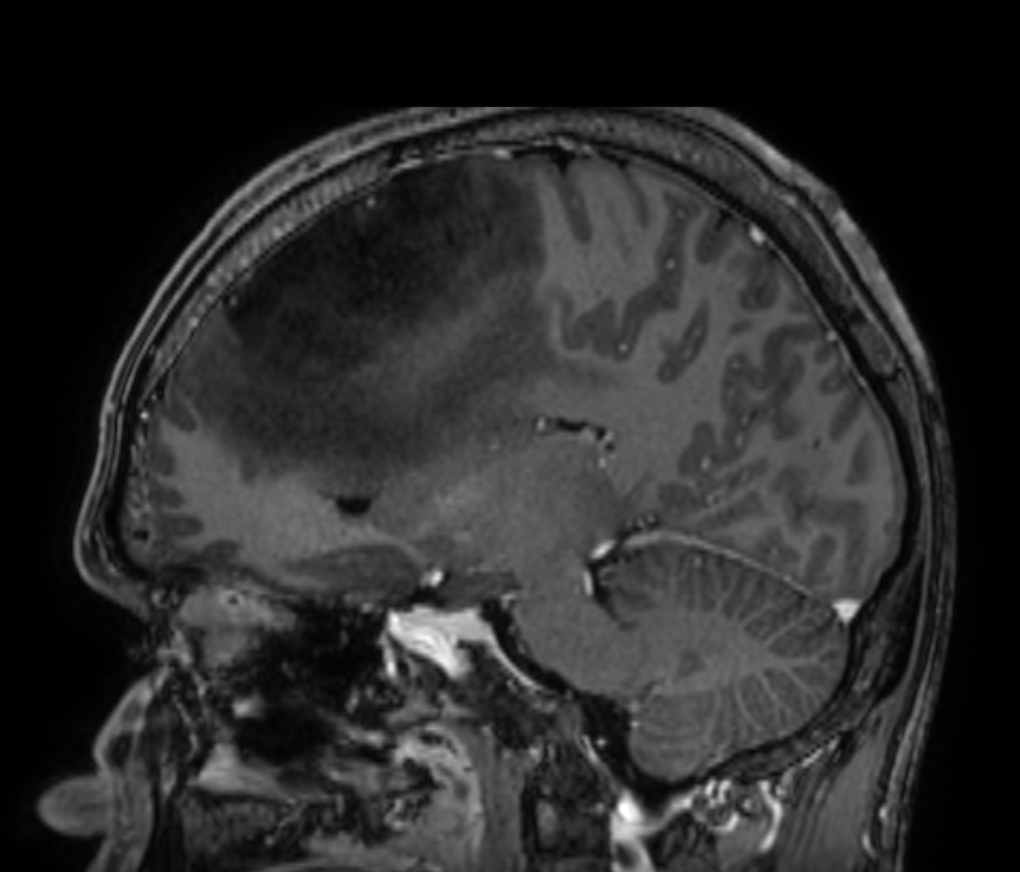

3D VIEW - T2w FLAIR (sagittal reformat)

3D VIEW - T2w FLAIR

3D VIEW - T2w FLAIR (coronal reformat)